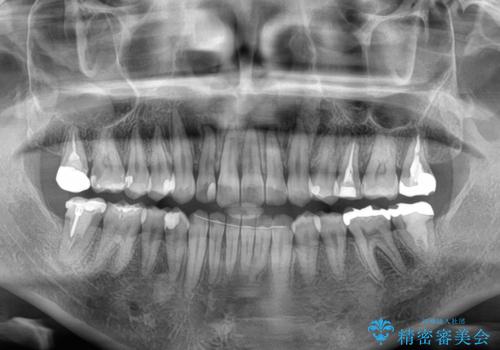

- 上下前歯の叢生を気にして来院された患者様です。

軽度な叢生であり、安価で短期間の治療を規模されていたため、インビザライン・モデレートを用いて矯正治療を行うこととしました。